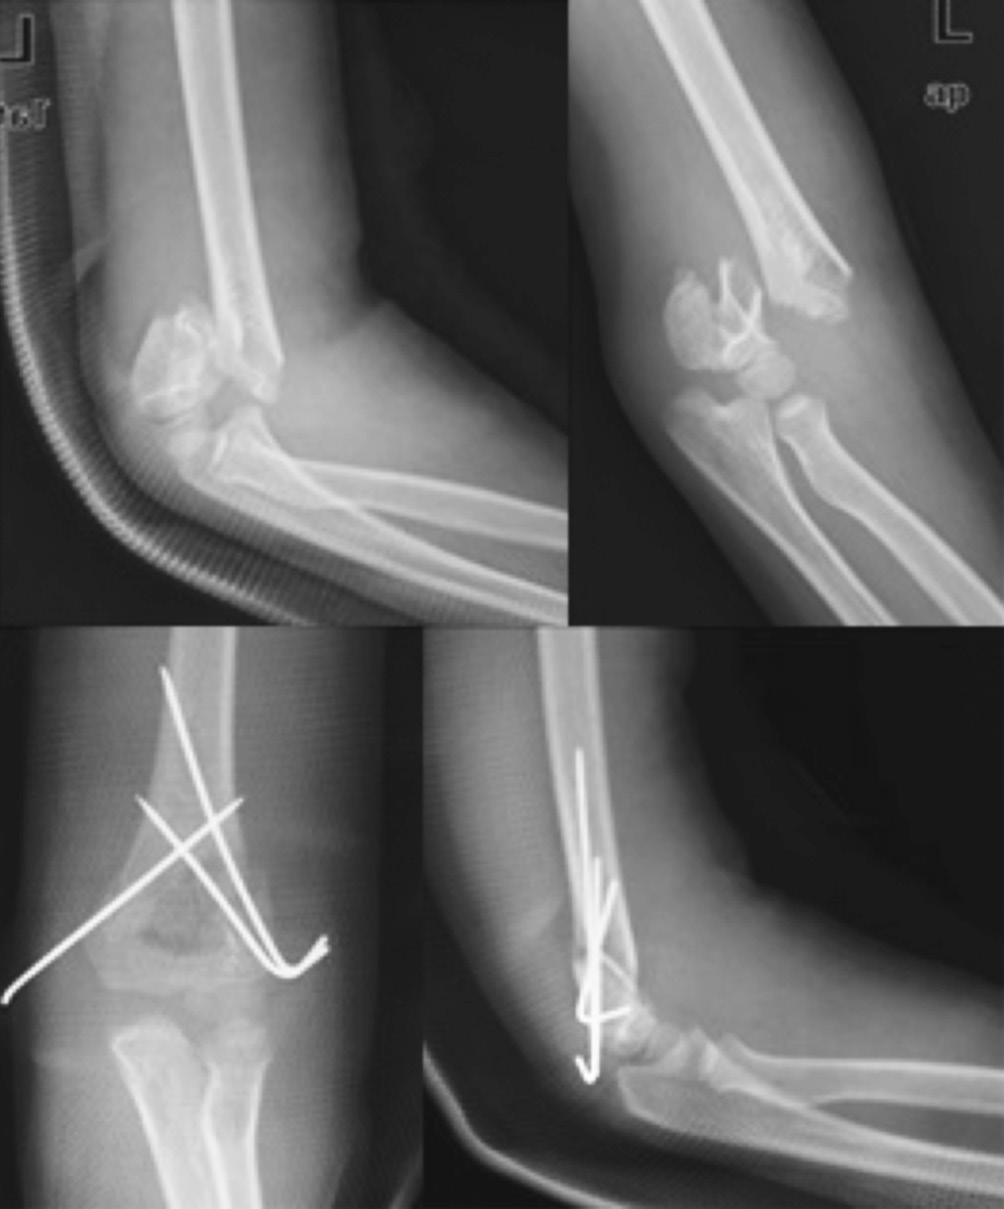

A total of 29 cases were injured before 4 PM while a total of 45 were injured after 4 PM. There was only one case of injury between midnight and early morning (Fig. 2). There were 11 cases of nerve injury: 4 cases of radial nerve, 4 cases of median nerve, and 3 cases of anterior interosseous nerve. All nerve injuries recovered at the final follow up. The average of total operation time was about 40 ± 17 minutes. Fixation of two at the lateral side and one at the medial was performed in 58 cases (Fig. 3). All patients had bone union without secondary intervention with no complications such as infection or deformity.

Fig. 3. Postoperative radiographs showing well fixed supracondylar fracture with K-wires